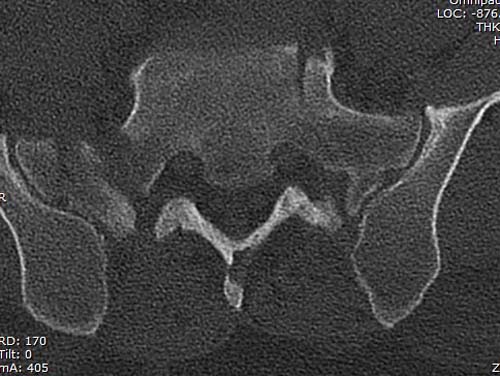

КТ, при детальном рассмотрении виден перелом задних отделов крыла подвздошной кости

KT

Перелом заднего отдела крыла подвдошной кости доказывает, что задние связочные элементы подвздошно- крестцового сочленения интактны, и такой перелом известен как “Сrescent fracture’. Переломы разделяется на 4 типа, и до фиксации надо хорошо изучить топографию перелома, иначе винт может попасть в линию перелома и не удержать фиксацию.

Но вам повезло, двумя винтами смогли зацепить и репонировать переломо-вывих. Обычно такие переломы надо фиксировать спереди или сзади пластиной или шурупом, т.е. создать дополнительную стабильность крыла, кроме перкутанной фиксации.